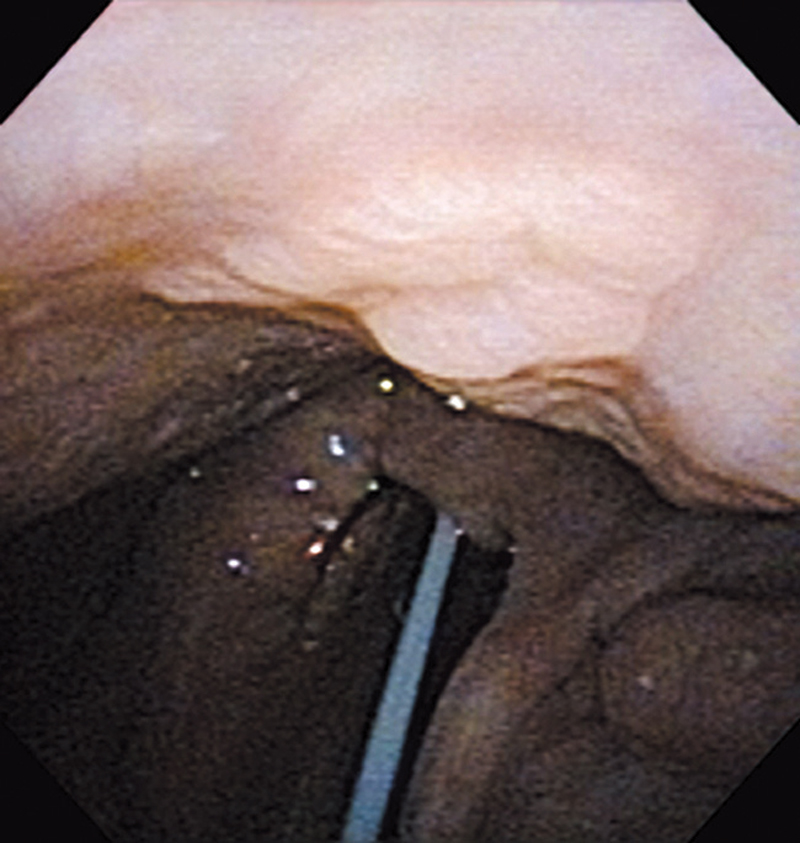

The lesion was detected in the oropharyngeal posterior wall in a laryngopharyngoscopic NBI examination during follow-up after treatment of a carcinoma in the floor of the mouth.

It was recognized under NBI as a lesion with a brownish area, and the close-up view additionally showed scattered brown dots. In the conventional white light image, the same area was seen as a reddening lesion.

The lesion was 5 x 3 mm and located on the back of the soft palate, and was diagnosed as a carcinoma in situ.